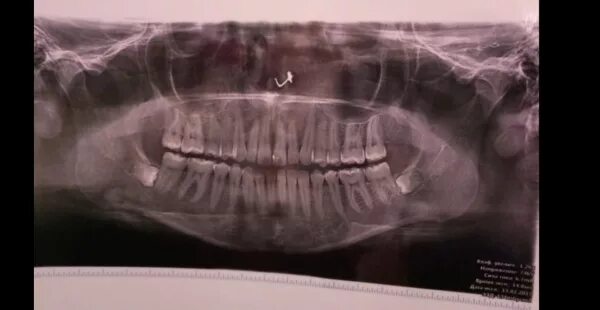

Что делать если заклинило челюсть